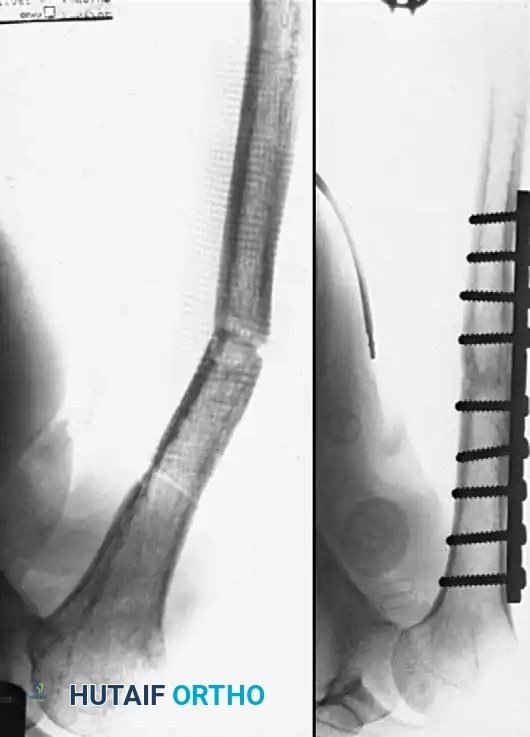

Metatarsals

Nonunions of the metatarsals are relatively uncommon due to the robust vascular supply and the splinting effect of adjacent intact metatarsals and intrinsic musculature. When they do occur, they are almost exclusively the result of poor apposition of the fracture fragments, severe soft-tissue stripping during initial injury or surgery, or deep infection.

They occur most frequently in the distal third of the bone, particularly following highly comminuted crush injuries or displaced spiral fractures where soft tissue interposition prevents cortical contact.

Management Principles:

* Asymptomatic Nonunions: Often require no surgical intervention, provided the patient has a plantigrade, pain-free foot.

* Symptomatic Nonunions: Require surgical takedown. The fibrous pseudarthrosis must be excised back to bleeding, healthy bone.

* Fixation: Rigid internal fixation using low-profile mini-fragment plates (2.0 mm or 2.4 mm systems) is the gold standard. If a segmental defect is created after debridement, structural autograft (e.g., iliac crest) is required to maintain metatarsal length and prevent transfer metatarsalgia.